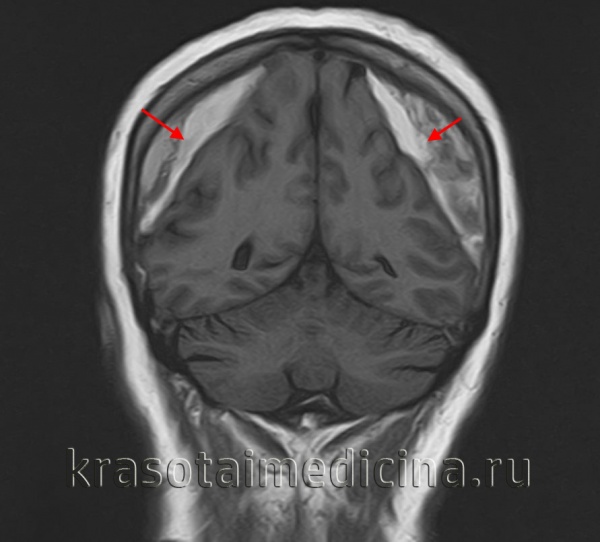

о МРТ-наиболее информативный метод визуализации хронической субдуральной гематомы (хСДГ):

- Хроническая субдуральная гематома (хСДГ) часто имеет гиперинтенсивный сигнал (вследствие наличия метгемоглобина) на Т1-, Т2-, PD-ВИ, а также FLAIR

- МРТ обеспечивает более информативную визуализацию мембраны и тромба:

Утолщение или обширное распространение неомембран или тромба в сочетании с масс-эффектом являются показанием для эвакуации хронической субдуральной гематомы (хСДГ) и мембранэктомии